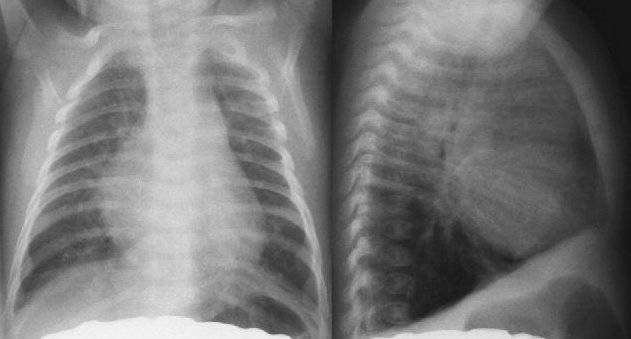

Если, с помощью рентгенографии грудной клетки, будет наблюдаться увеличение сердца, прежде всего, необходимо выявить причину патологии и оценить процент фиброзной ткани.

- RX. Для оценки сердечной тени.

Необходимы тщательный сбор анамнеза и подробное физикальное исследование для исключения клинически известных причин столь значительной КМГ: пороков сердца, артериальной гипертензии, ИБС, некоторых вторичных кардиомиопатий, например, алкогольной, миокардита Абрамова-Фидлера. ЭКГ практически у всех больных выявляетс различные нарушения ритма и проводимости (желудочковые экстрасистолы, блокады ножек пучка Гиса, АВ-блокады, желудочковая тахикардия, мерцательная аритмия), иногда — инфарктоподобные изменения и истинные инфаркты миокарда, гипертрофию различных камер сердца. Рентгенологически обнаруживается увеличение размеров сердца, повышение кардиоторакального индекса (КТИ). КТИ более 0.55 считается неблагоприятным прогностическим признаком.

Более полную и точную картинку можно получить с помощью рентгена. Именно данный способ является одним из наиболее популярных для диагностики различных патологий внутренних органов. Изучив полученные снимки, врач определит, увеличилось ли сердце. Если были обнаружены изменения, то диагностируют кардиомегалию.